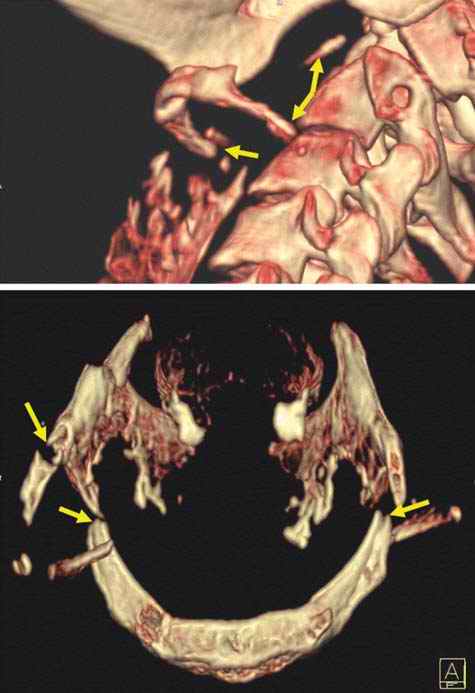

As is well known from clinical medicine, mid-face fractures can also extend over the maxilla and the zygomatic bone (Figure D3.2.8). These fractures arise from a direct impact to the face. Depending on the involved structures, these fractures are classified as Le Fort I-III. This classification can be difficult, especially in cases of vehicle accidents, where, due to the massive damage, multiple fractures are often seen. In such cases, the Le Fort classes overlap (Figure D3.2.9). Mandibular fractures occur due to punches, falls, and vehicle accidents, to name just a few mechanisms. Direct fractures are seen paramedially, whereas indirect fractures are mostly located in the region of the joint and the mandibular body.

Postmortem imaging can display such possibly telltale injuries in a rapid and nondestructive manner, thus sparing the face from further disfigurement or the pathologist from missing a potentially important finding.